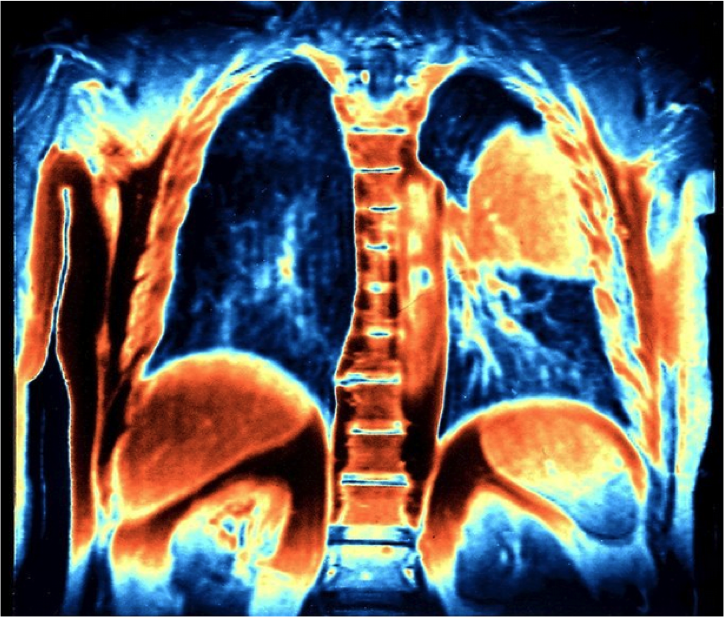

彩色磁共振成像扫描右上方橙色肺部恶性肿瘤, 单纯化疗已不再是肺癌的标准治疗!